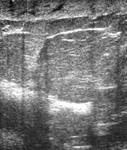

Imagem ultrassonográfica do espessamento da pele em paciente com câncer de mama inflamatório

Cortesia da Dra. Nancy Pile, Universidade de Louisville; usado com permissão